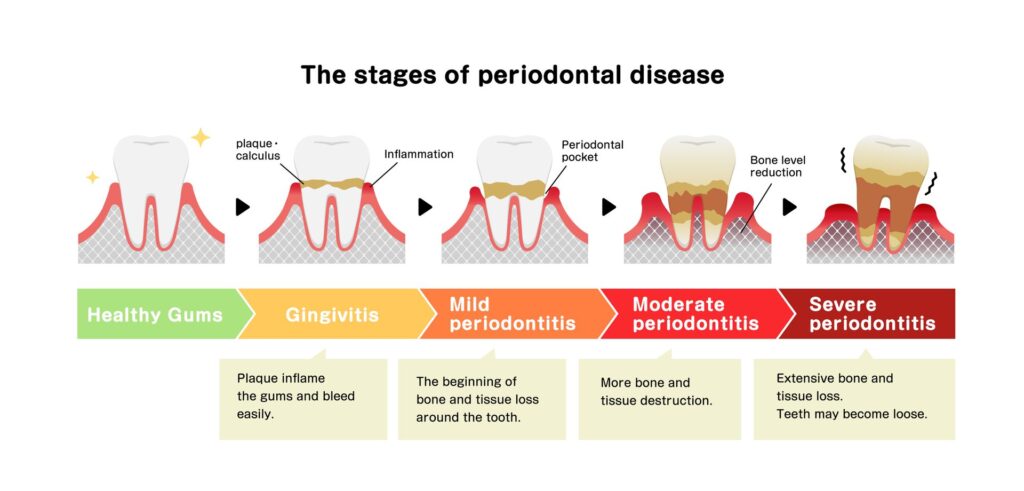

Periodontal disease occurs when bacterial growth in your mouth damages the soft tissue of your gum.

When left untreated, it ultimately destroys the bone supporting your tooth, leading to tooth loss.

In its earlier stages, it is known as gingivitis – an occurrence of gum inflammation. As a result, it causes your gums to bleed even while brushing mildly.

However, not all gingivitis will lead to periodontal diseases (or periodontitis).

You may experience mild gum inflammation, which you may easily ignore. However, it is recommended to have it checked out to prevent the development of periodontal disease.